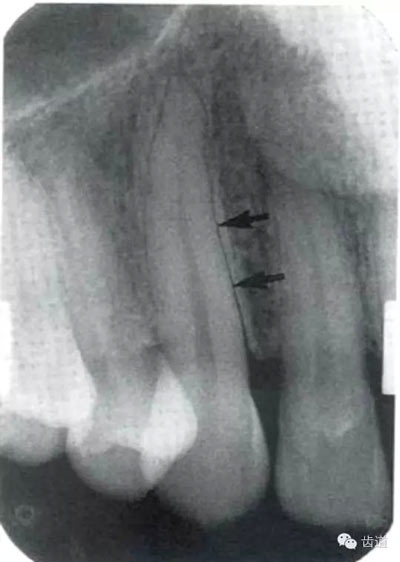

2)營養(yǎng)管:

常見于下頜前牙區(qū),在牙根之間的牙槽骨內(nèi)并與牙長軸平行的密度低的條狀影像。此為小血管進入牙槽突的影像。